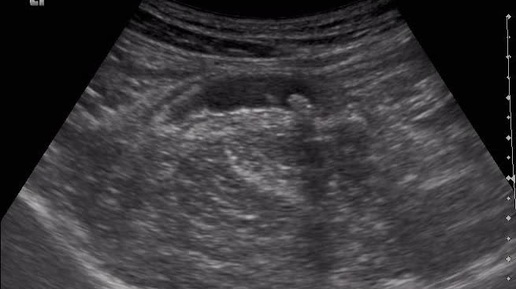

Ультразвуковые находки от врача УЗД Зорина Я.П.